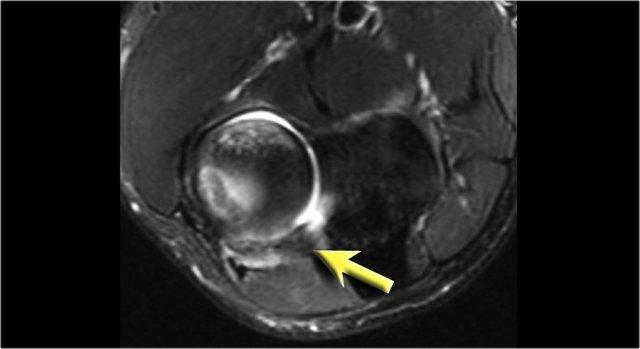

Những hình ảnh này của một cầu thủ bóng chày trẻ, xuất hiện với triệu chứng đau khuỷu tay lúc 14 tuổi.

Hình ảnh T2W-fatsat cho thấy phù tủy xương và có thể có gãy xương dưới sụn.

Rõ ràng là có người đã bảo cậu bé tiếp tục ném bóng, vì cậu quay lại ba năm sau khi 17 tuổi và bạn có thể thấy điều gì xảy ra khi người ta thúc ép quá mức để biến những đứa trẻ này thành vận động viên chuyên nghiệp.

Hình ảnh T1W cho thấy sự phân mảnh (mũi tên vàng) với một mảnh xương tự do (mũi tên đỏ).

Hình ảnh T2W chứng minh rằng mảnh xương không ổn định do có tín hiệu cao giữa mảnh xương và xương cánh tay.

Khi nội soi khớp, có thể thấy sự lõm xuống và không đều của sụn chỏm con.

First the loose bodies were taken out.

Sau đó, thủ thuật OATS thường được thực hiện, mà chúng ta sẽ thảo luận ngay bây giờ.